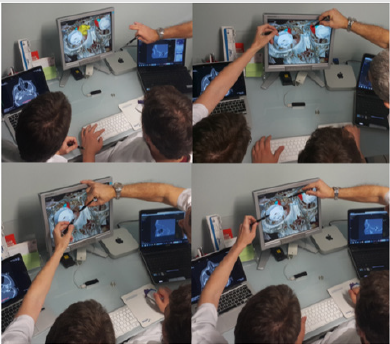

Our team has long been the leader of advanced surgery in otorhinolaryngology-head and neck surgery (3D-CAS/1994 [16,17], tele-3D-CAS/1998 [18,19], touchless “in the air” surgery/2015 [2,6,10]). Is also the today’s team of contemporary innovative surgery, concerning the highest quality level, the highest level of user experience in the daily routine practice, which use appropriate DICOM images and “gesture motions” viewer industry? Our newest project proposal [2,6,10] aims to enable further shifting of such educational and clinical frontiers based on well-known solutions from VR, while involving more experts from different scientific fields that could shape the research and educational process in different, interesting ways, as for example medical diagnostics, surgery “in the air” in virtual world that are simulated and modeled before the real surgery [6,20-22], as well as surgeries in virtual anatomic surroundings that are assisted by 3D-digitizer with six degrees of freedom [11,23-26] (Figure 2).

Figure 2: Involvement of more experts from different scientific fields in preoperative analysis/teleanalysis in virtual surroundings by using of motion tracking camera for navigation through the data. We used voice command for easier contactless navigation through the application (3D anatomy of the patient’s head.